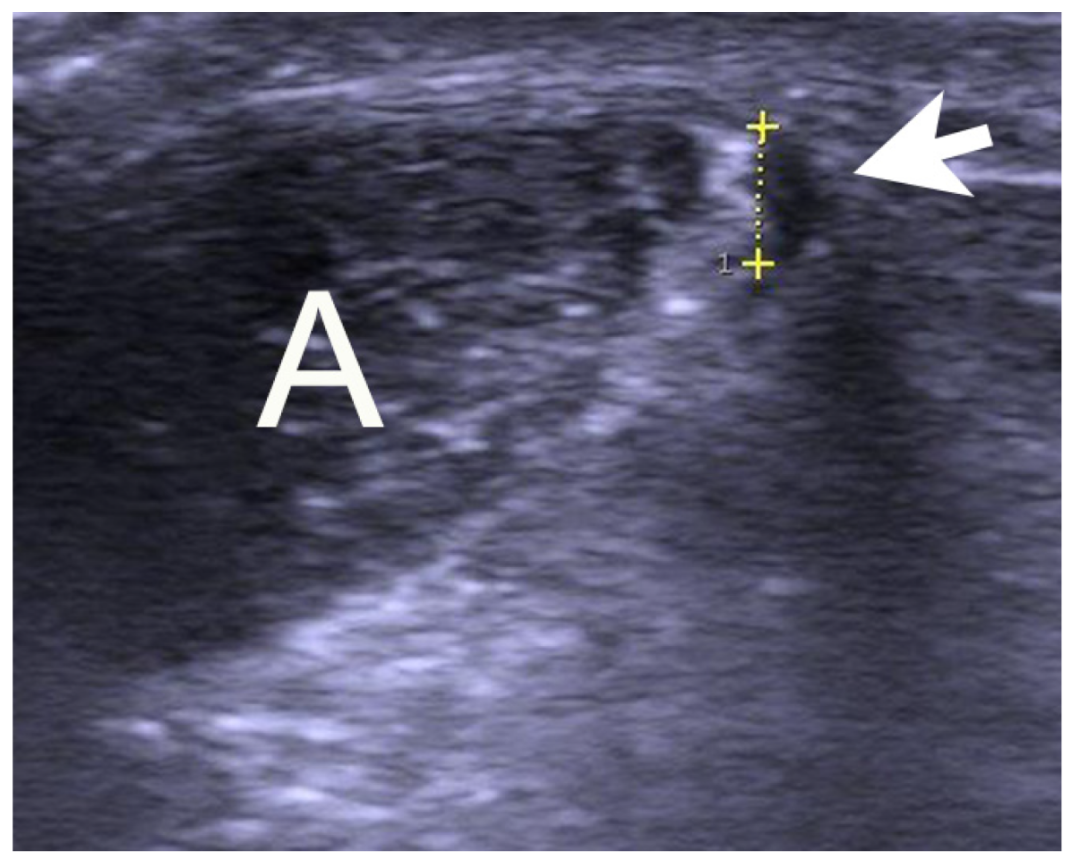

图:跟腱中段腱病(mid-portion tendinopathy)

这张图重点展示了中段型腱病:

“A” 区显示跟腱组织在这一段的厚度增加、低回声改变,提示退变;

这个位置通常在距跟骨附着 2–6 cm 范围内,是临床最常见的慢性跟腱病区域。

这种类型常被误认为“肌肉拉伤”或“单纯劳损”。